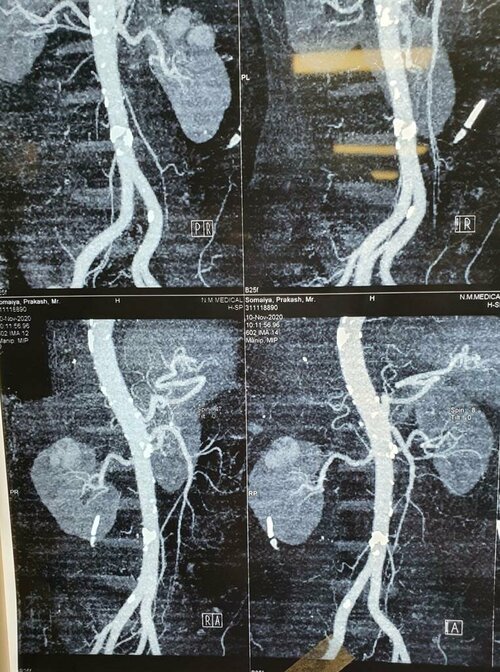

A  68 years old man came to best urologist in Pune, Dr. Bhoopat Bhati with pain in abdomen  post Angioplasty with Diabetes and Hyp...